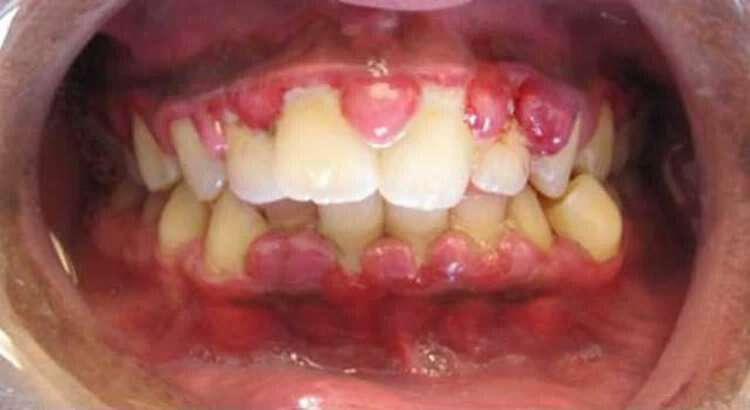

Diş eti kanaması

Evet, C vitamini eksikliğinde iskorbüt hastalığı ortaya çıkar. C vitamini eksikliğinin ilk belirtileri arasında halsizlik, yorgunluk, kolay morarma ve diş eti kanaması yer alır. Eksiklik ilerledikçe eklem ağrıları, ciltte lekelenme ve iskorbüt hastalığının diğer belirtileri ortaya çıkar.